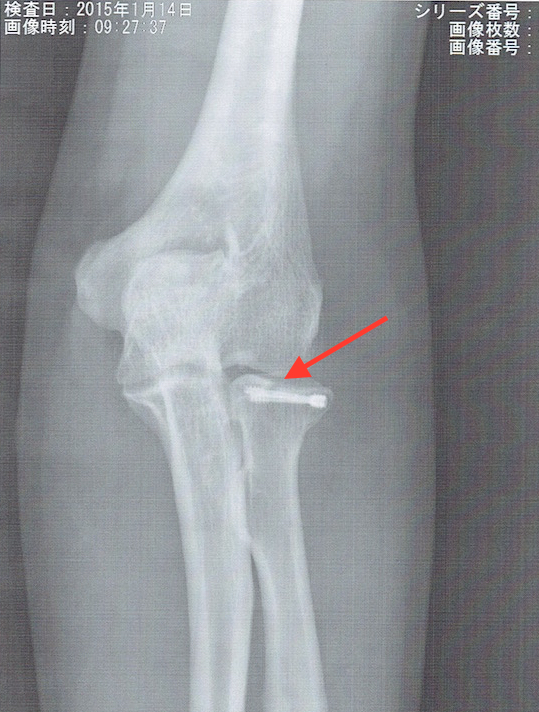

今までにもブログにも何度となく書きましたが、昨年6月のある日の深夜に、当院のドアを壊して押し入ろうとした強盗に私が気がつき、犯人を捕まえようと追いかけたところ、凶器(ナイフとバール)で襲われ、顔面や腕の骨折等の重症を負わされた事件がありました。

生まれて初めての骨折、全身麻酔、手術、入院、刑事さん達とおこなった実況見分、そして検察庁や裁判所へ行ったこと、法廷での証言…